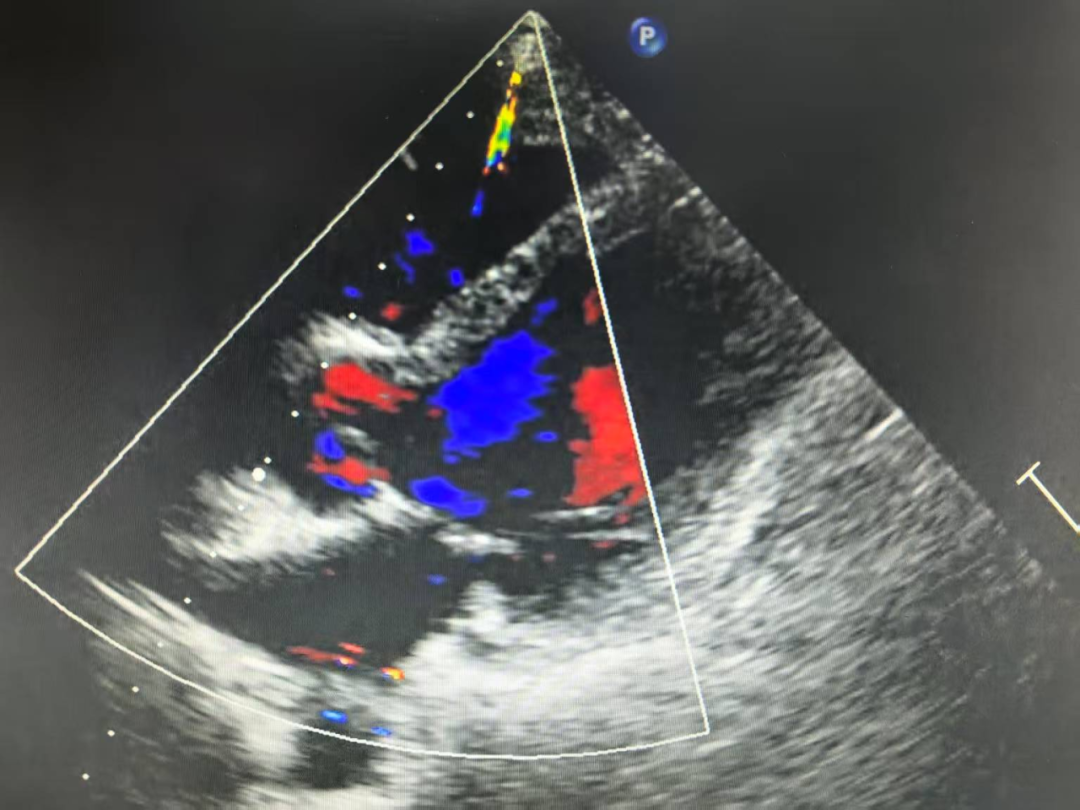

10月14日,彭磊因身体极度不适,状态极差,被家人紧急送往医院,并直接送入ICU接受救治。通过心脏彩超检查发现,心功能EF值急速下降到26%(正常值在50%-70%左右),随后更是跌至10%,肝肾相继衰竭。在当地医院,他不得不依靠ECMO(体外膜肺氧合技术)、IABP(主动脉内球囊反搏)和CRRT(血液净化)三台“救命机器”维持生命体征。

其间,通过血液检测,医生已明确彭老师患上的是病毒性心肌炎,心肌损伤极其严重。然而,经过连续多天的抢救,彭老师病情仍在恶化,心功能EF值下降到10%左右,出现了心脏扩大、心力衰竭的临床征象,必须依赖机械辅助维持心脏的跳动。